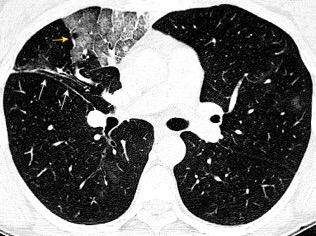

WINDEMERE” . SÍNDROME DE LADY

Forma indolente. Supresión de la tos. Língula y LM los más frecuentemente afectados. Bronquiectasias.

Coexistencia con nódulos centrilobulillares y patrón en mosaico muy sugerente.

Micobacteria atípica

Frecuencia en “clusters” familiares. Factores genéticos de sensibilidad del huésped a la infección pulmonar.

Colombo RE et al. Familial Clustering of Pulmonary Nontuberculous Mycobacterial Disease. Chest 2010./ Olivier KN. Lady Windermere Dissected: More Form Than Fastidious. Ann Am Thorac Soc. 2016/Martínez S et al. The many faces of pulmonary Nontuberculous Mycobacterial infection. AJR. 2007